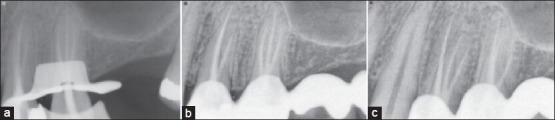

Unusual anatomical configurations must be considered in the radiographic and clinical evaluation during the endodontic treatment. The canal anatomy maxillary first and second premolar has been studied extensively and the presence of three canals is relatively rare especially in the maxillary second premolar. The occurrence of three canals with separate foramina in both the first and second premolar is shown to be in extremely low percentages and has been documented as practically non-existent in Asian populations. This article describes a case of a maxillary first and second premolar with three canals each.

在牙髓治疗的影像学和临床评估中,必须考虑异常的解剖结构。上颌第一和第二前磨牙的根管解剖结构已被广泛研究,三根根管的情况相对少见,尤其是在上颌第二前磨牙中。上颌第一和第二前磨牙中出现三个独立根尖孔的根管的比例极低,并且据记载在亚洲人群中几乎不存在。本文描述了一例上颌第一和第二前磨牙均有三根根管的病例。